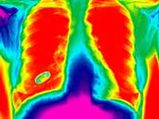

Lung Cancer Treatment With Diabetes Drug

Lung Cancer Treatment With Diabetes Drug -